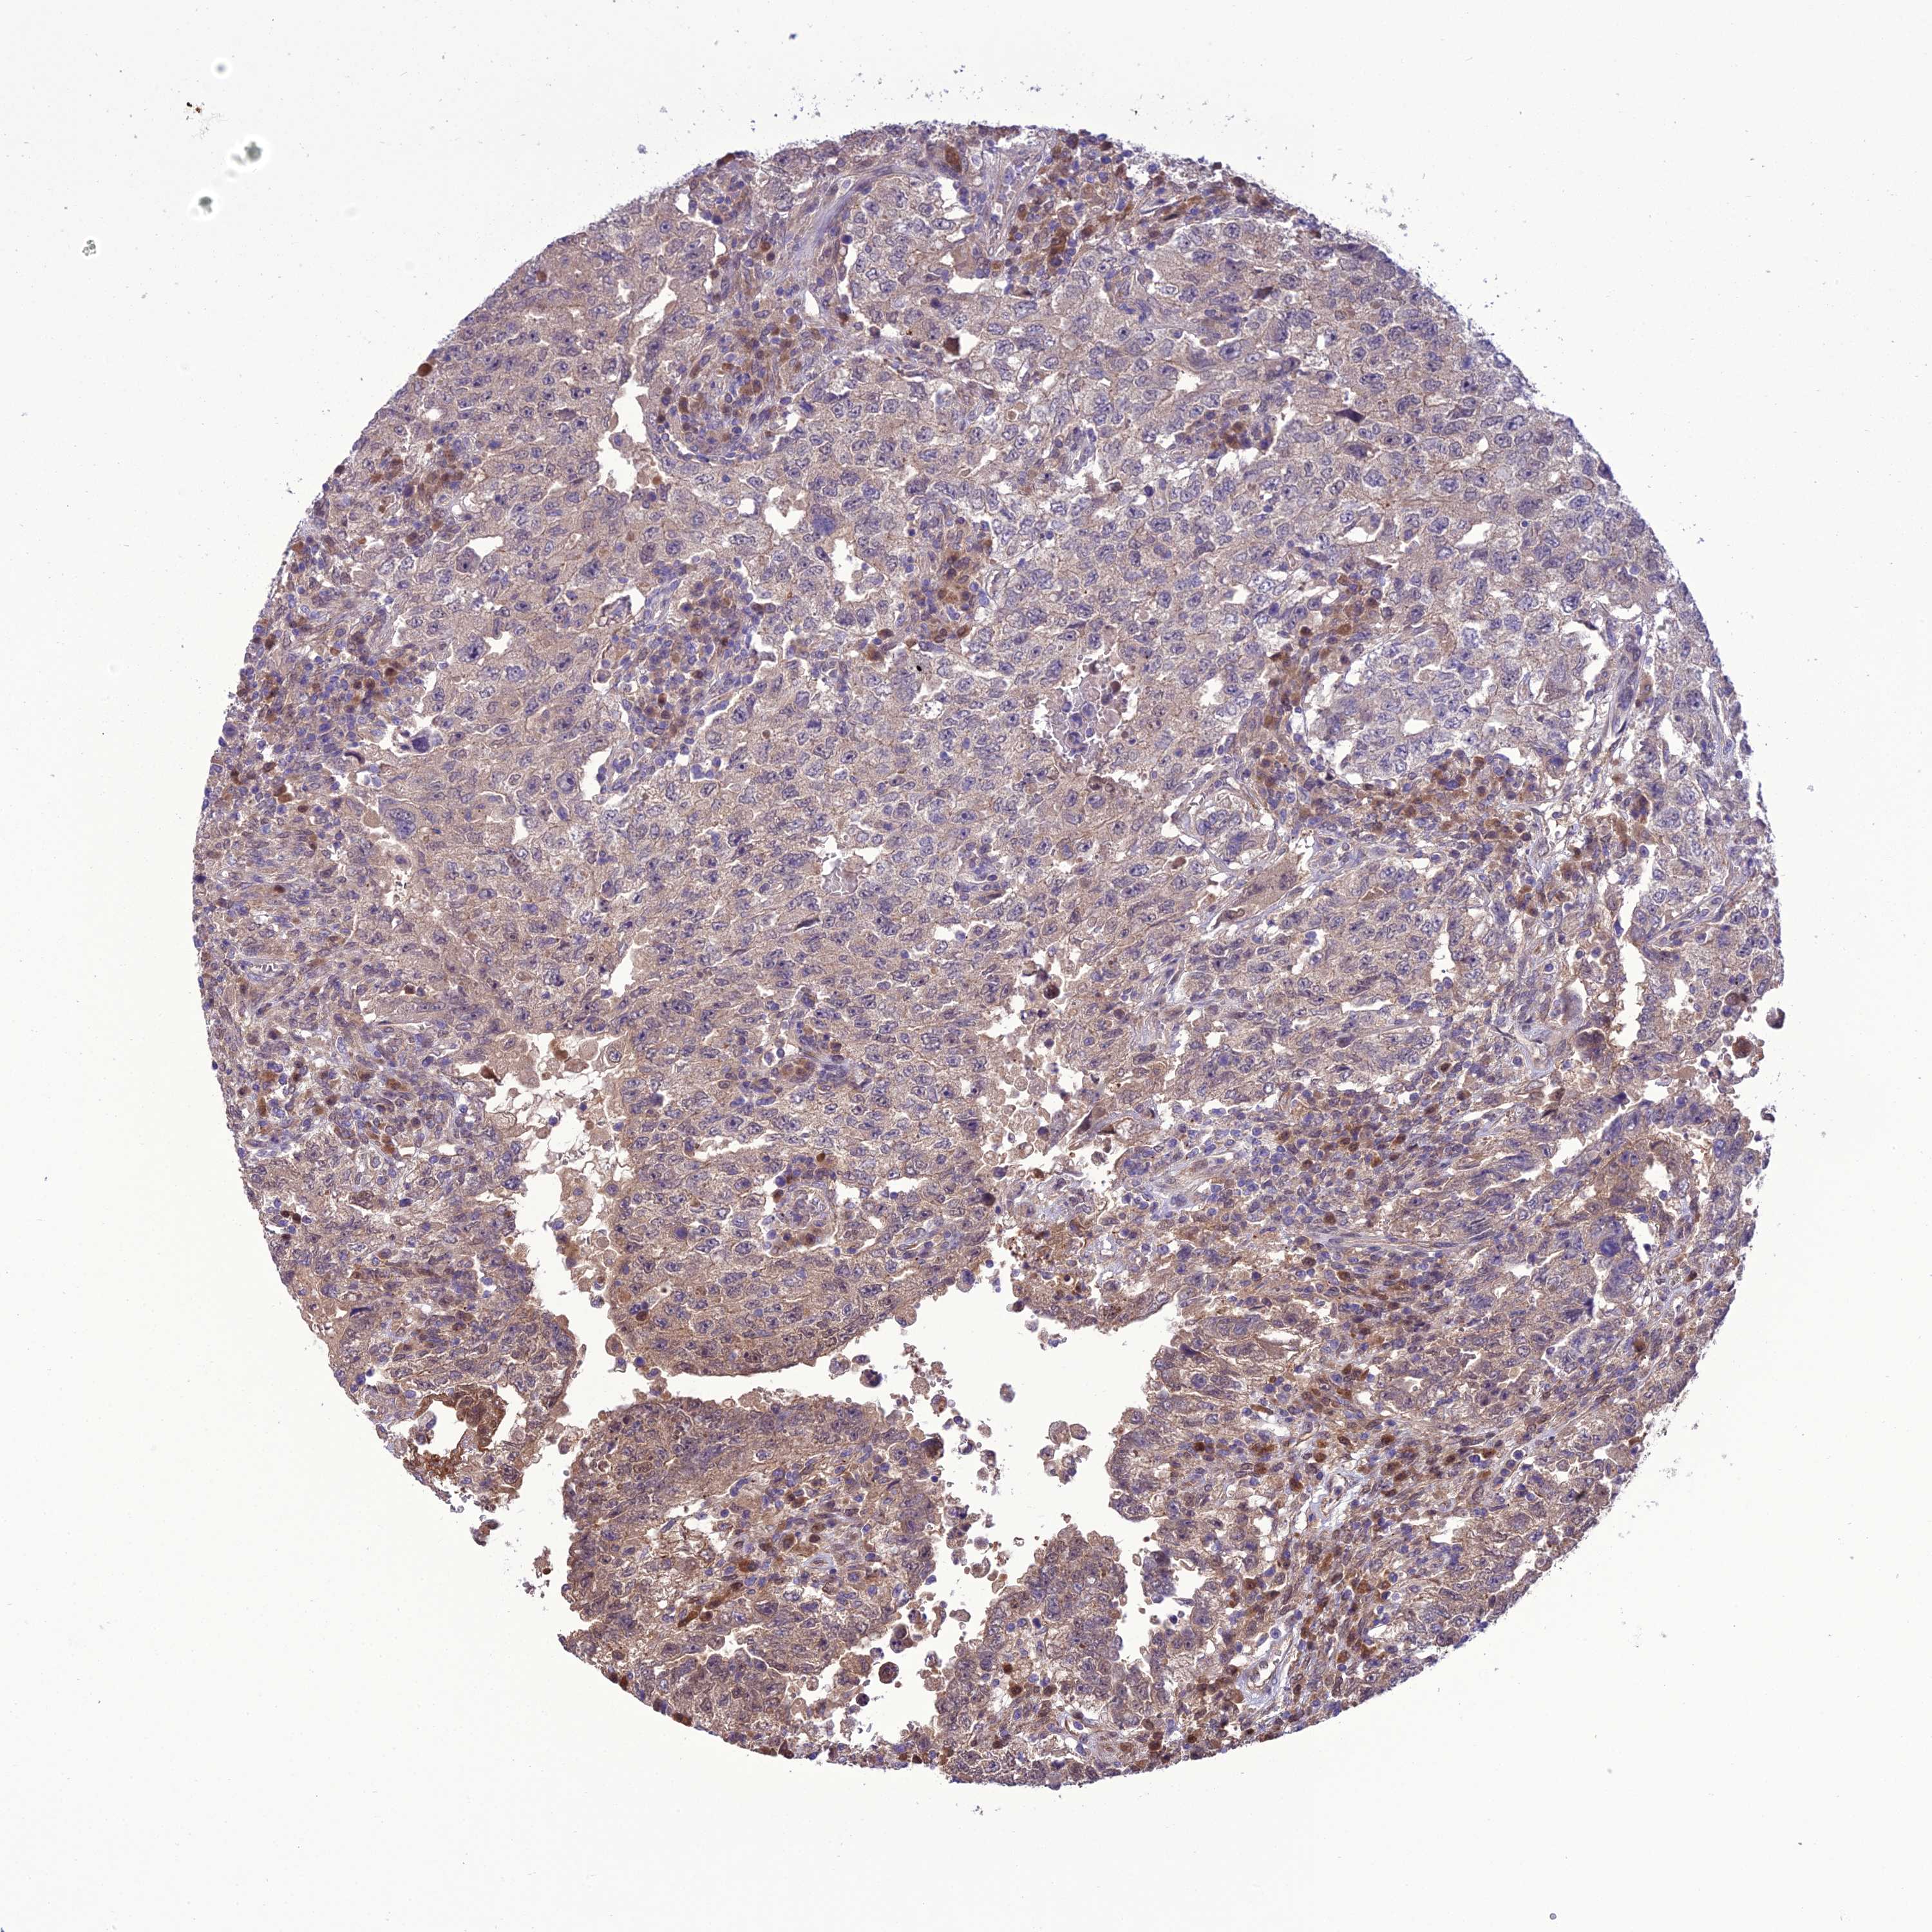

TESTIS CANCER - Protein expressioni

A mouse-over function shows sample information and annotation data. Click on an image to view it in a full screen mode. Samples can be filtered based on level of antibody staining by selecting one or several of the following categories: high, medium, low and not detected. The assay and annotation is described here.

Note that samples used for immunohistochemistry by the Human Protein Atlas do not correspond to samples in the TCGA dataset.

Antibody stainingi

Antibody staining in the annotated cell types in the current human tissue is reported as not detected, low, medium, or high, based on conventional immunohistochemistry profiling in selected tissues. This score is based on the combination of the staining intensity and fraction of stained cells.

Each image is clickable and will lead to virtual microscopy that enables deeper exploration of all samples and also displays staining intensity scores, fraction scores and subcellular localization as well as patient and tissue information for each sample.

Antibody HPA045415

Carcinoma, Embryonal, NOS

Seminoma, NOS